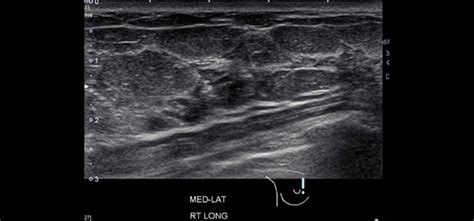

Breast ultrasound uses sound waves to make a computer picture of the inside of the breast. On ultrasound, a breast cancer tumor is often seen as hypoechoic, has irregular borders, and may appear spiculated. On ultrasound it will be hypoechoic with spiculations radiating away from the nipple. You might not need any further tests if everything looks normal. A specialist looks at the ultrasound pictures. However, in rare cases, breast cancer can be the cause of gynecomastia so, a full mammographic. Mammogram imaging may show skin thickening, but often there is no distinct mass found on physical examination or … Both malignant and benign lesions may show either circumscribed or poorly defined margins. Notice that there is some fibroglandular tissue on the right, while on the left there is only subcutaneous fat. If a solid lump shows on the scan you might need to have. There is a higher incidence in people from china and africa due to hyperestrogenism secondary to parasitic liver disease. 17 years experience general surgery. This breast cancer ultrasound image shows changes related to breast cancer that are not seen as microcalcifications or a mass or lump.

On ultrasound it will be hypoechoic with spiculations radiating away from the nipple. Rapid onset of symptoms (redness, swelling, warmth, itching, skin thickening) are hallmarks of the disease. 17 years experience general surgery. Mass due to cancer on ultrasound, a breast cancer tumor is often seen as hypoechoic, has irregular borders, and may appear spiculated. Is the abnormal enlargement of rudimentary male breast tissue. You may have an imaging test, like a mammogram or ultrasound, for an inside look. This breast cancer ultrasound image shows changes related to breast cancer that are not seen as microcalcifications or a mass or lump. This test is often used when a change has been. Other ultrasound findings that suggest breast cancer include: Malignant disease in men just looks like malignant disease in women. A specialist looks at the ultrasound pictures. Dcis on mri may create an area of irregular enhancement of the mri dye into the breast. On the flip side, there are benign (not cancerous) breast changes which can mimic breast cancer as well.

Dcis on mri may create an area of irregular enhancement of the mri dye into the breast. The exact cause of breast. Is the abnormal enlargement of rudimentary male breast tissue. X trustworthy source mayo clinic educational website from one of the world's leading hospitals go to source research suggests that men are more likely to ignore breast lumps than women, but early. Ultrasound is useful for looking at some breast changes, such as lumps (especially those that can be felt but not seen on a mammogram) or changes in women with dense breast tissue. Breast cancer in men just looks like breast cancer in women. Other ultrasound findings that suggest breast cancer include: Breast ultrasound is often used to examine some types of breast changes. You may get a biopsy. These cancers present as a unilateral painless subareolar mass. There is a higher incidence in people from china and africa due to hyperestrogenism secondary to parasitic liver disease. While it may look like a fuzzy, spotty television screen with different shades of grey to a patient, the ultrasound technician and the radiologist use these images to diagnose masses and tumors. Breast ultrasound is an imaging test that uses sound waves to look at the inside of your breasts.